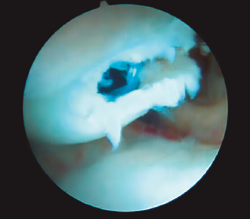

Figura 9. Reducción de fragmento distal con gancho palpador introducido por portal mediocarpiano radial; visión desde el portal mediocarpiano ulnar.

Una vez que se ha comprobado la colocación de la aguja, se realiza la medición de la longitud del tornillo, se avanza la aguja guía hacia volar para permitir la extensión de la muñeca, minimizando el riesgo de rotura del material. A continuación, a través de los portales MCR y MCU se verifica la reducción obtenida de la fractura; si no se ha conseguido una reducción aceptable, se retira por volar la aguja dejándola en el fragmento distal; a continuación, se procede a la reducción de los fragmentos de forma indirecta, mediante manipulación e hiperextensión de la muñeca o utilizando agujas de Kirschner a modo de joysticks para movilizar los fragmentos, o de forma directa, manipulando el fragmento distal con un gancho palpador o con un periostotomo que se introducirán por el portal MCR (Figura 9).